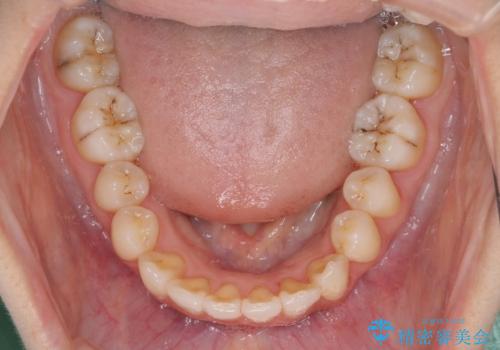

マウスピース矯正は毎日しっかりと装着することがとても大切です。

こちらの方はしっかりと指示を守って装着してくださったため、予定通り治療を終えることができました。